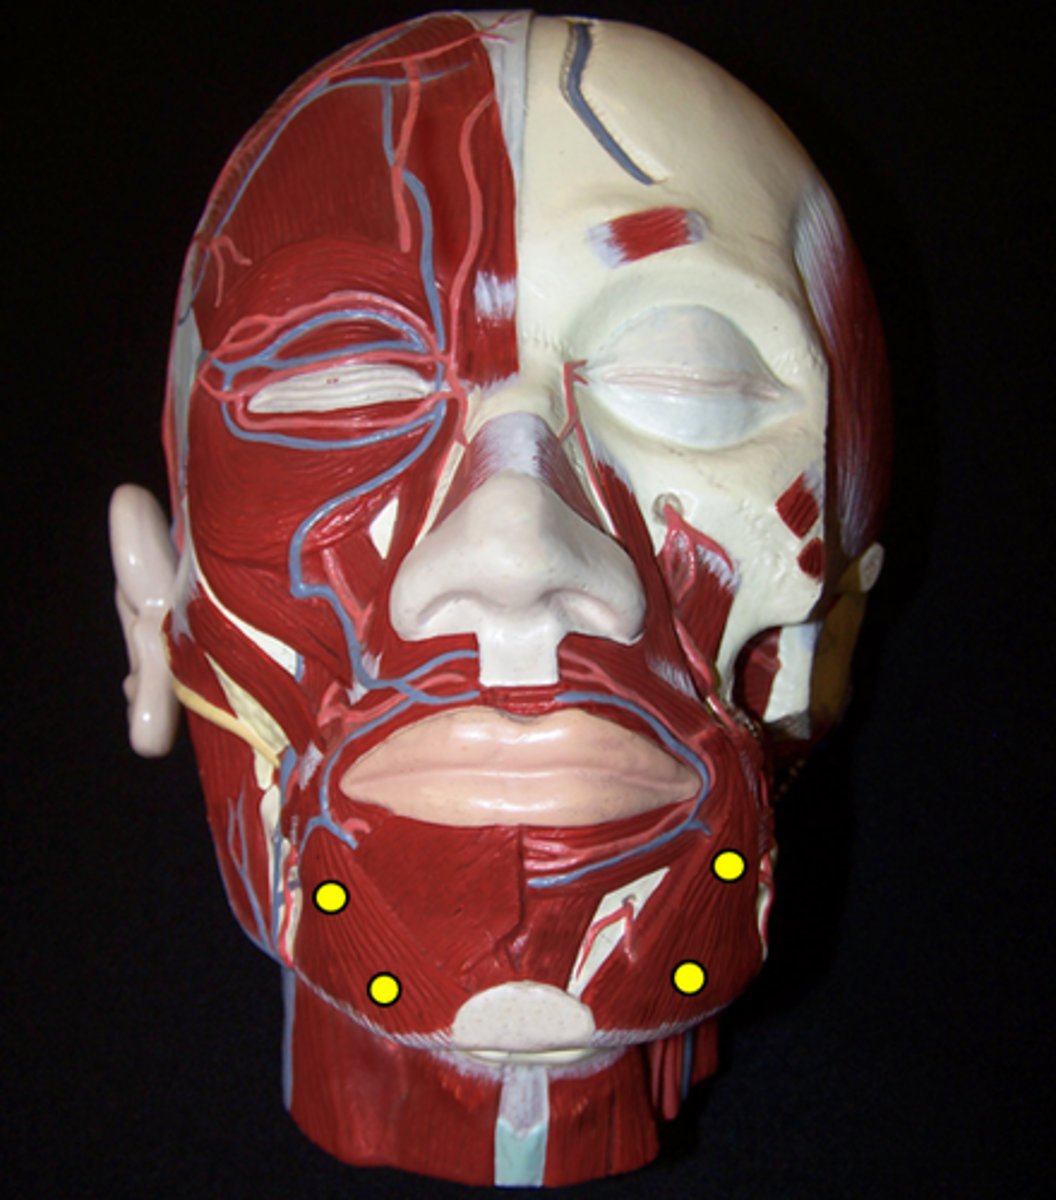

Depressor Anguli Oris

Depressor Labii Inferioris

Mentalis

Buccinator